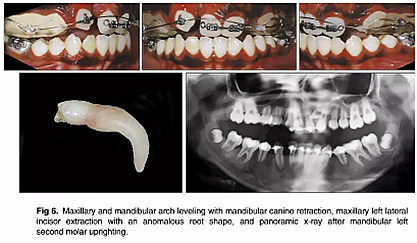

幾個月后,拔除上頜乳尖牙,應(yīng)用0.018×0.025英寸規(guī)格的亞歷山大固定矯治器; 上頜中切牙的對齊由0.014英寸的鎳鈦弓絲開始,而上頜左側(cè)尖牙則是腭側(cè)萌出。在下頜弓中,應(yīng)用舌側(cè)弓和第二前磨牙托槽來實現(xiàn)解除旋轉(zhuǎn)(圖4)。然后,上頜右側(cè)尖牙用0.016英寸的鎳鈦弓絲重新定位,并且使用0.016英寸的不銹鋼片段弓維持中切牙的位置。在下頜弓中,應(yīng)用帶有開放式螺旋彈簧的截面鋼絲直立左側(cè)第二磨牙。它在第一磨牙影響下發(fā)生嚴重傾斜,受到第三磨牙的壓迫(圖5)。如全景片所示,下頜左側(cè)第二磨牙直立得以實現(xiàn)(圖6)。1年后,去除上頜擴弓器,上下牙弓完全吻合。在上下牙弓中,用0.017×0.025英寸的鎳鈦弓絲進行整平。上頜左側(cè)尖牙被移至側(cè)切牙位置; 下頜第一前磨牙被拔除,尖牙開始縮回。

隨后,由口腔頜面外科醫(yī)生(圖6 ; 圖7)拔除左右側(cè)側(cè)切牙,并使用直角弓來旋轉(zhuǎn)上頜磨牙并改善牙弓形態(tài); 在下頜弓中,尖牙的牽引繼續(xù)(圖7)。